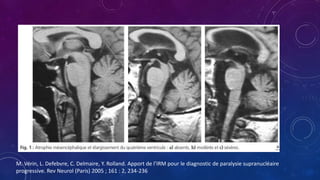

• Las anormalidades frecuentemente encontradas en RM son

• Dilatación del cuarto ventrículo

• Aumento del ángulo interpeduncular

• Hiperintensidad del pálido interno en T2

• Discreta hiperintensidad en el borde del putamen en T2

• Otros signos encontrados son

• Dilatación del acueducto de Silvio

• Dilatación del tercer ventrículo

• Hiperintensidad puntiforme en el mesencefalo

M. Vérin, L. Defebvre, C. Delmaire, Y. Rolland. Apport de l’IRM pour le diagnostic de paralysie supranucléaire

progressive. Rev Neurol (Paris) 2005 ; 161 : 2, 234-236